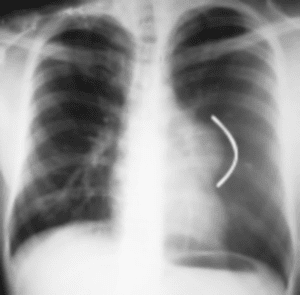

En la radiografía de tórax, se aprecia imagen densa, homogénea, redondeada, bien definida en región mediastinal, que comprende posiblemente al mediastino anterior (Figura. 1).

Figura 6. Radiografía Tele de tórax posoperatoria. Dentro de límites normales con buena disposición de las estructuras, se aprecia cuerpo extraño metálico (alambre quirúrgico).